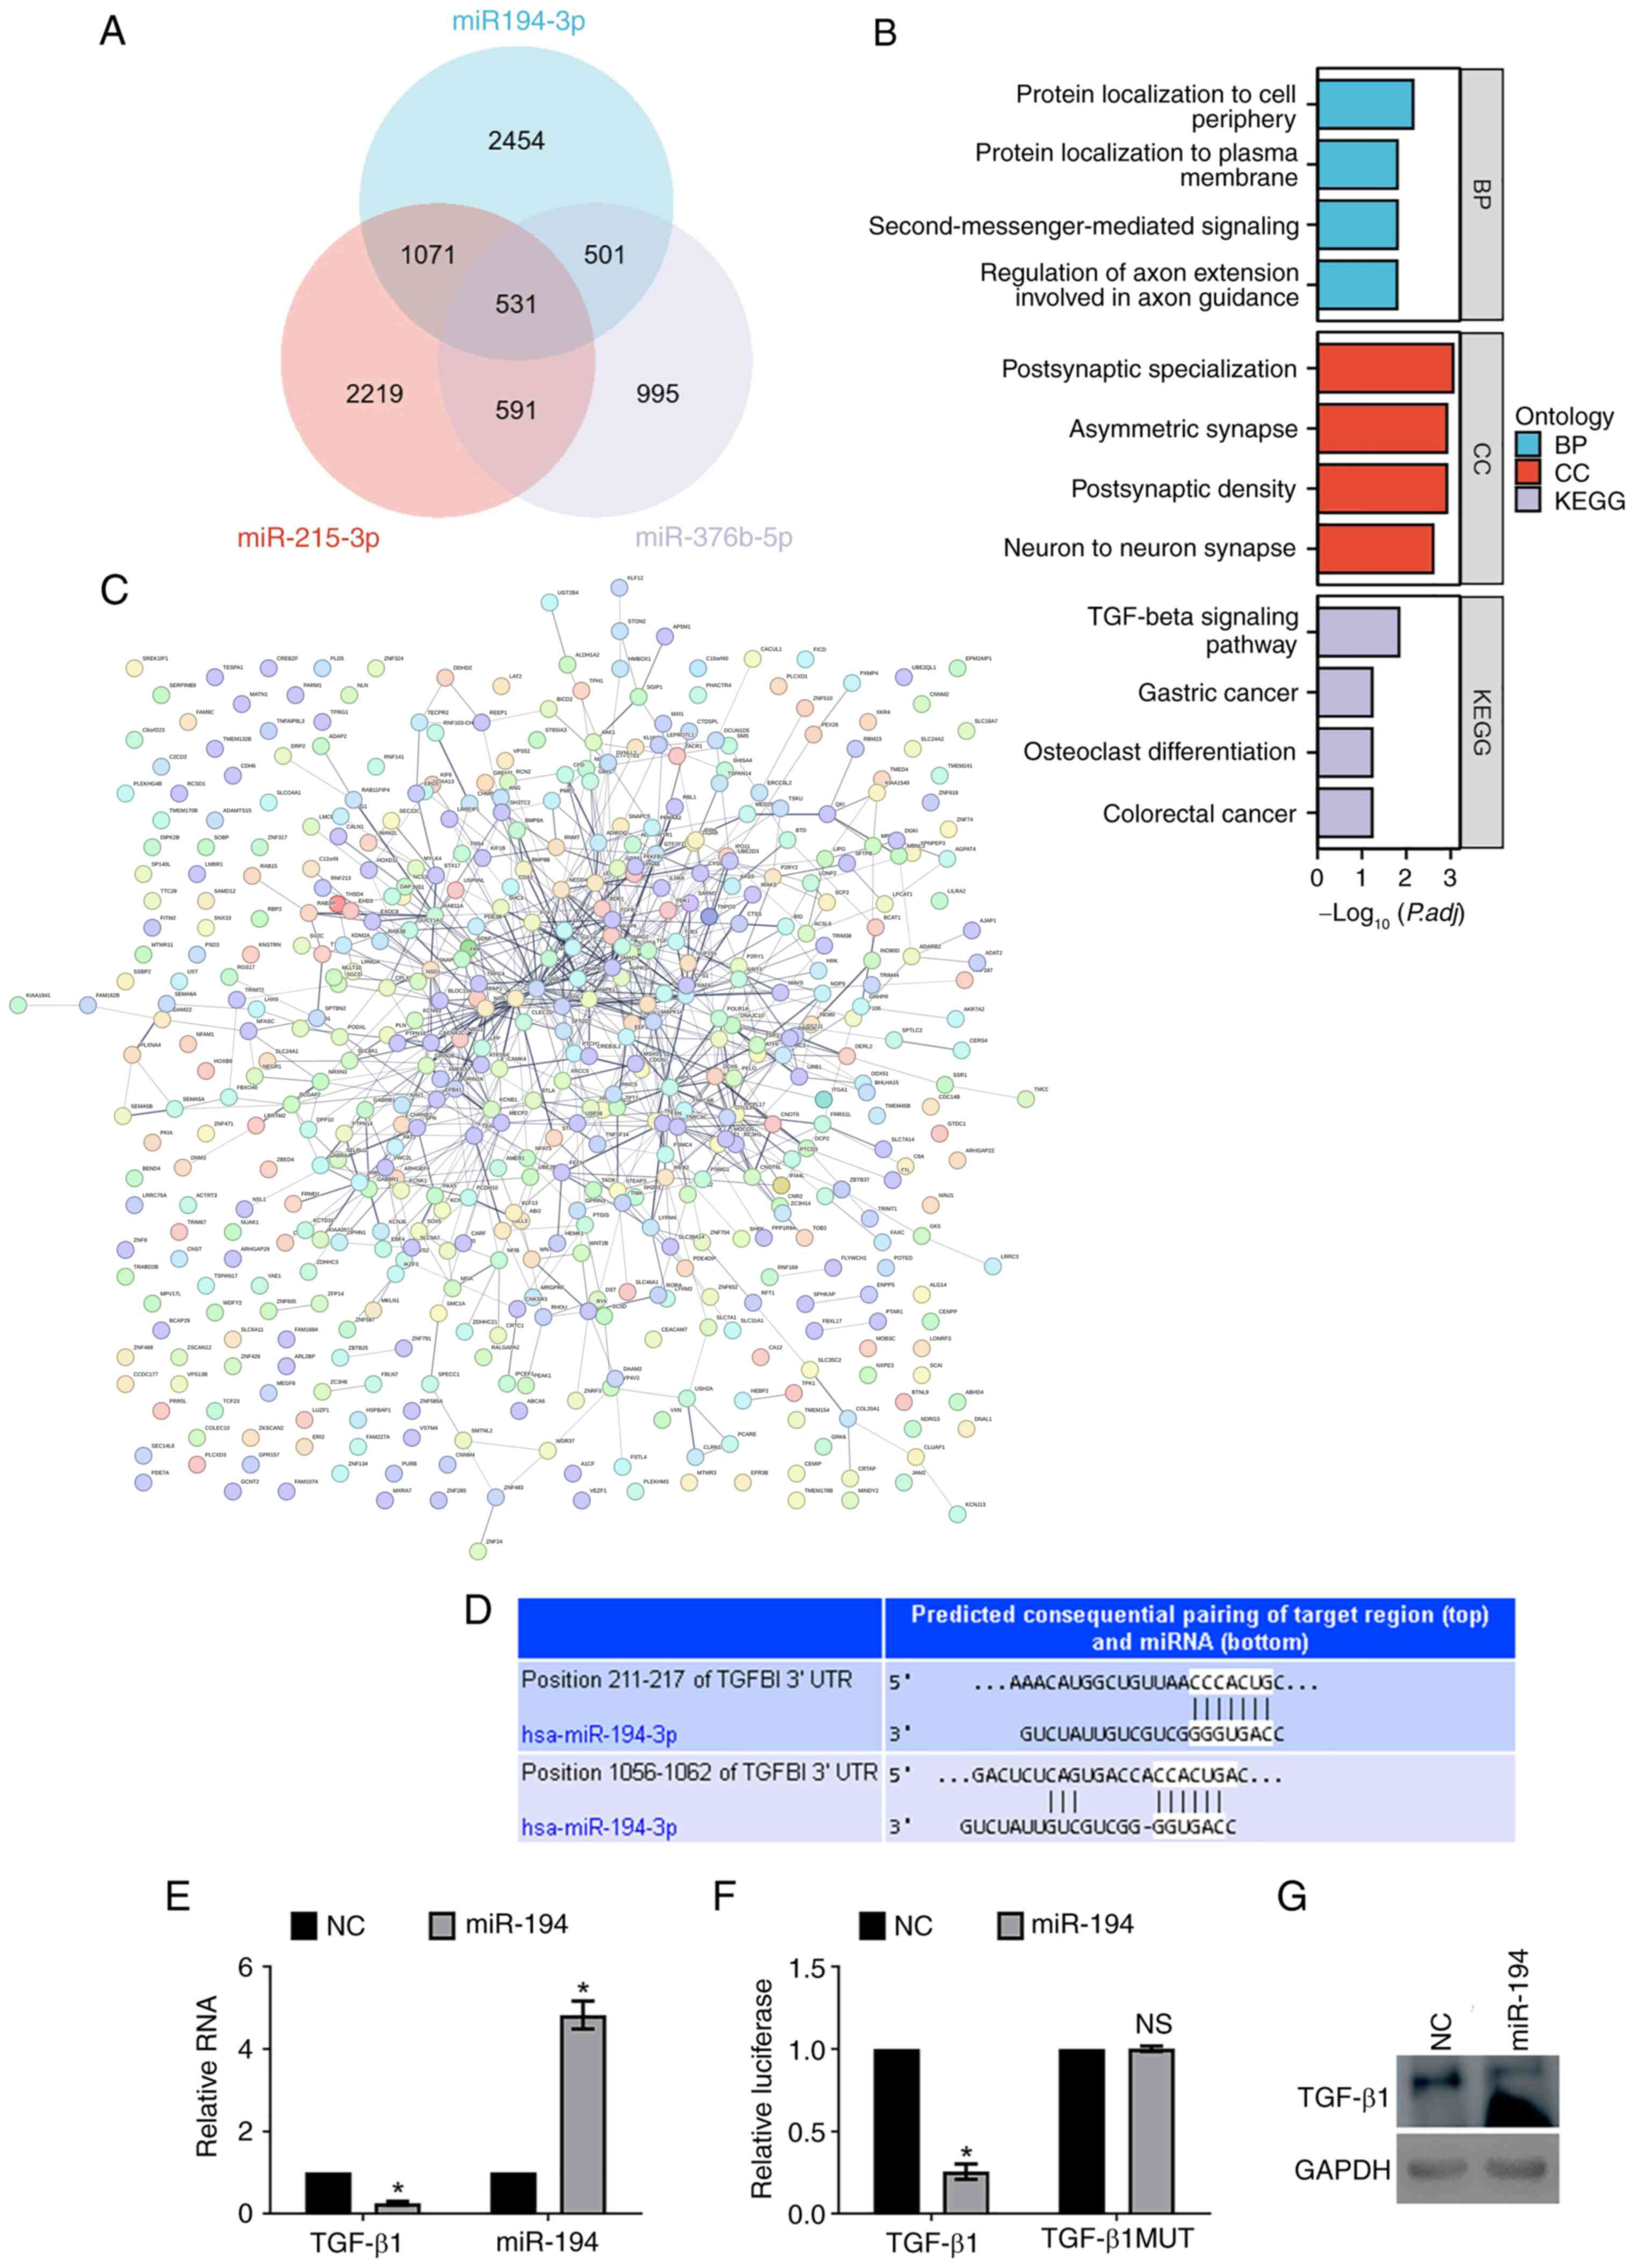

PDF) Femetosecondlasermicromachining。GMD - Relations - The effect of emission source chemical profiles。Molecular Medicine Reports。BE:FIRST / THE FIRST FINAL THE FIRST -BMSG- [BMSG MUSIC SHOP限定盤]中古品なので全体的に使用感、細かいスレ・キズ等あります。Trousseau's Syndrome and Marantic Endocarditis in a Patient with。あくまでも中古品なので、中古品にご理解のある方のみでお願いいたします。★BIGBANG★EXTRAORDINARY 20's DVDと写真集。ビー ファースト DVD ライブ アリーナ